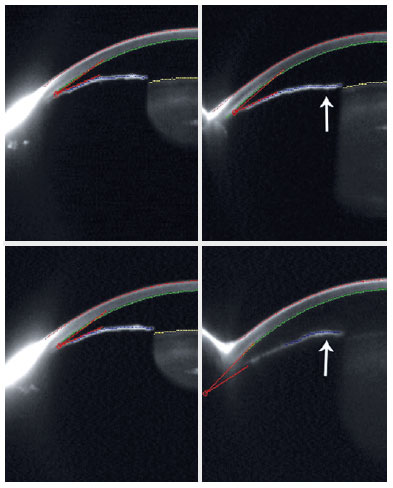

After receiving a topical combination of brimonidine tartarate 0.2% and timolol maleate 0.5% BID in OU associated with 1% pilocarpine TID in OS, the patient underwent a provocative test in a dark room, and IOP in OD increased by 8 mmHg. He then underwent peripheral laser iridotomy in both eyes (Figure 1).

04-fig01.jpg)

During the use of a topical combination of brimonidine tartarate 0.2% and timolol maleate 0.5% BID OU, the patient was invited to undergo a provocative test in a dark room. After the test, IOP increased by 10 mmHg OD and 8 mmHg OS, and peripheral laser iridotomies were successfully performed in OU (Figure 2).

04-fig02.jpg)